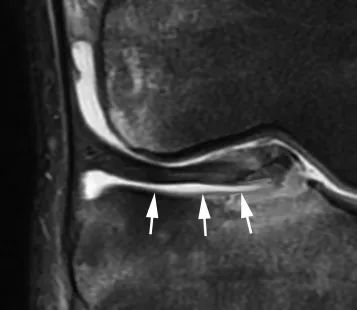

Un autre signe formel d'instabilité méniscale est l'identification d'un déplacement périphérique de fragments méniscals dans l'évidement méniscal fémoral ou l'évidement fémoro-tibial.Ces déplacements concernent presque exclusivement le ménisque médical et sont une complication de certains cas de fente horizontale dans 10 % des cas.Les coupes coronales et transversales sont le meilleur moyen d'identifier ces fragments.

Ceci est le résultat d'une blessure violente et est dû à une rupture du ligament ménisco-tibial et à un décollement de la partie médiale du ménisque.En IRM, le ménisque séparé est complètement entouré de liquide et semble 'flotter' sur le plateau tibial (Figure 12).

Figure 12 Ménisque flottant.Vue frontale de la densité de protons avec saturation des graisses.Le ménisque séparé est entouré de liquide, notamment entre sa face inférieure et le plateau tibial (flèche).